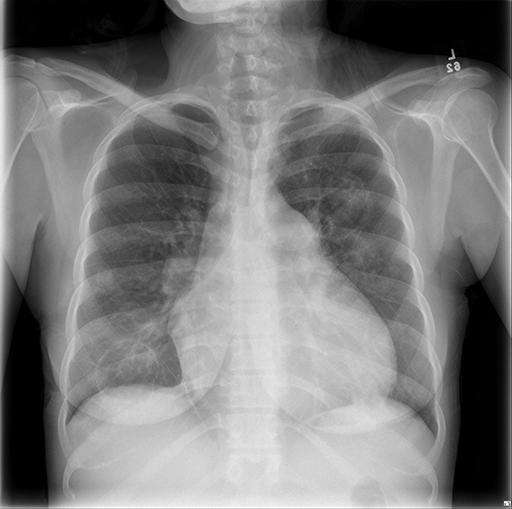

Vital signs and cardiopulmonary exam were normal. Basic labs and EKG were also normal. Due to an elevated D-dimer of 570 ng/mL, she had a CTA chest done.

CXR and CT Chest